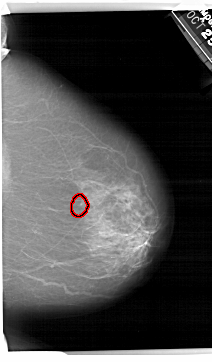

A_1495_1.LEFT_CC

RIGHT_CC LINES 6871 PIXELS_PER_LINE 4021 BITS_PER_PIXEL 12 RESOLUTION 43.5 OVERLAY

FILE: A_1495_1.RIGHT_CC.OVERLAY

TOTAL_ABNORMALITIES 1

ABNORMALITY 1

LESION_TYPE CALCIFICATION TYPE AMORPHOUS DISTRIBUTION CLUSTERED

ASSESSMENT 4

SUBTLETY 4

PATHOLOGY BENIGN

TOTAL_OUTLINES 1

BOUNDARY